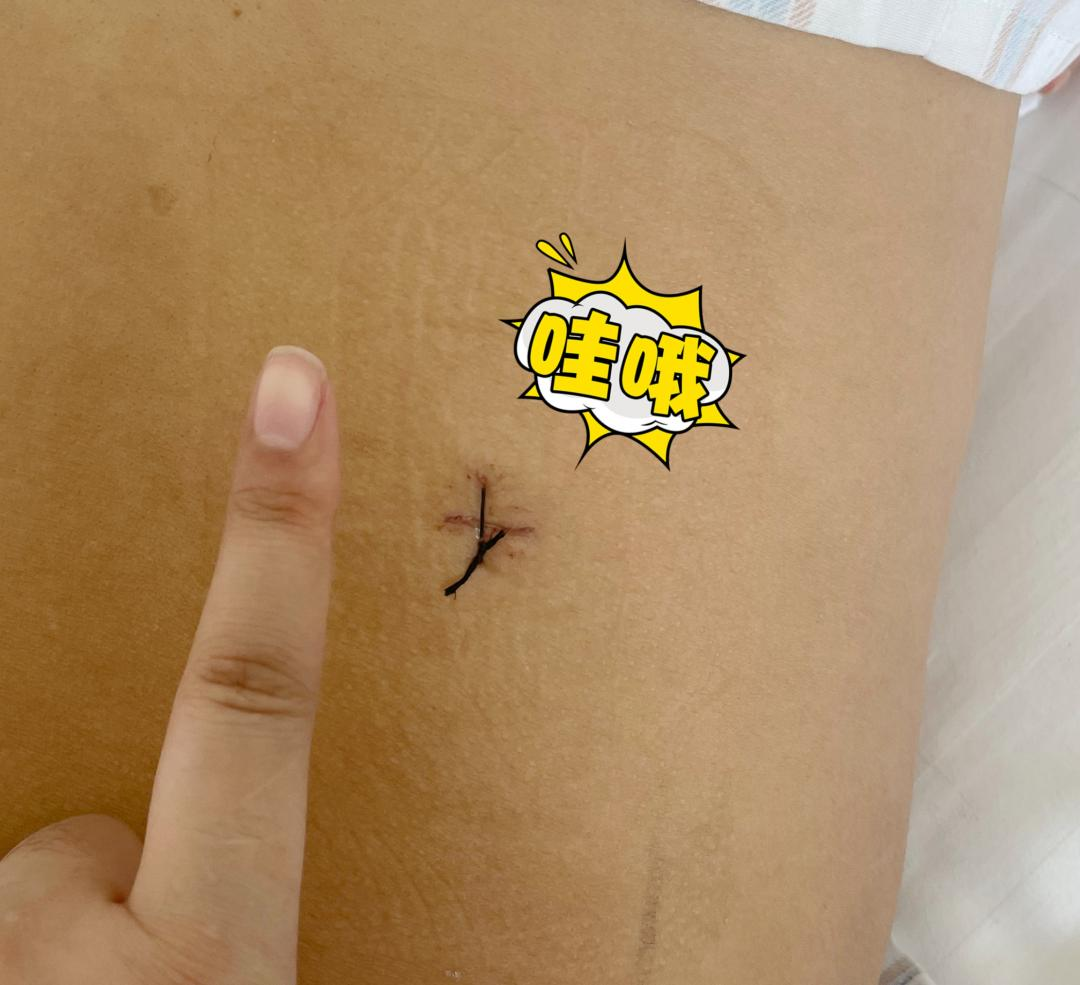

内镜下手术切口

本例患者术前双侧均有症状,内镜下单侧入路手术后双侧症状均缓解,且出血少,贫血患者更安全,恢复快。患者术后行走,笑容满面。